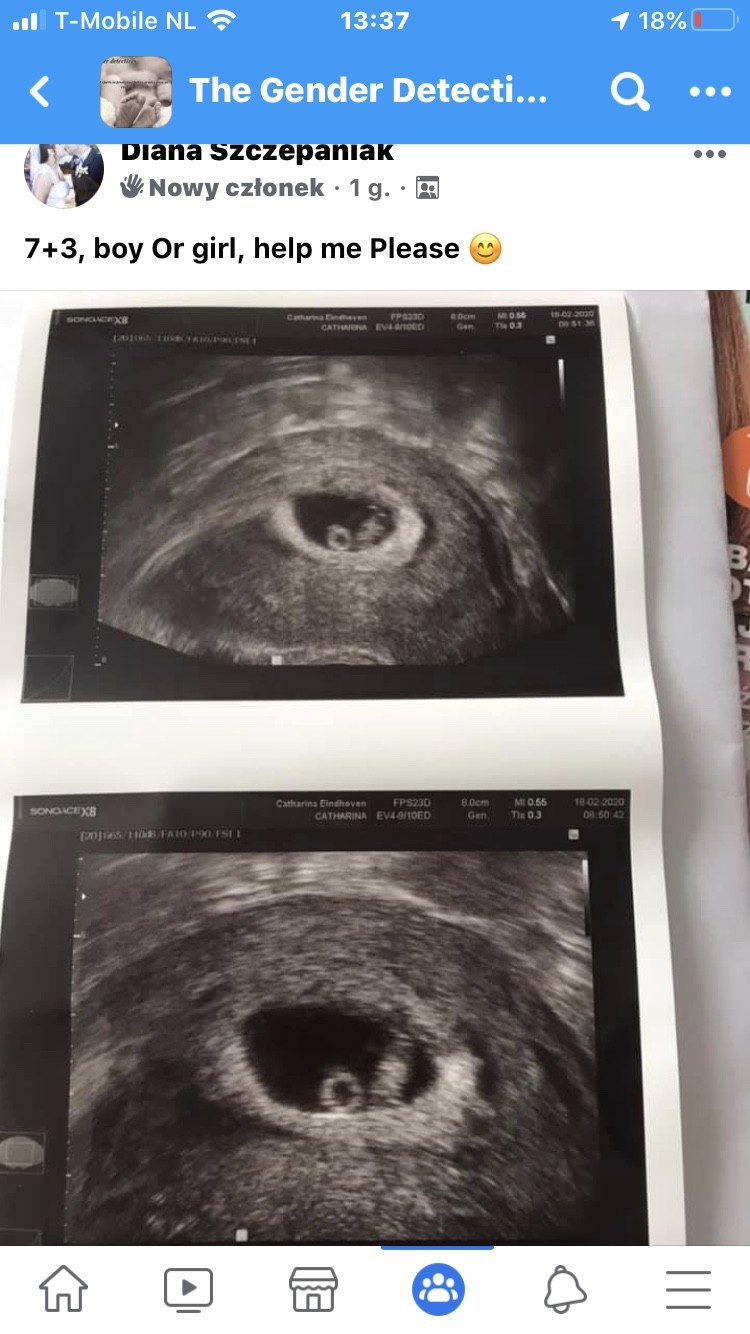

U mnie na razie wygrywa dziewczynka, ale jedna kobita dodała 2 różne sugestie do 2 zdjęć bo dodałam 2, do jednego ze dziewczynka do drugiego ze chłopiec

U mnie też 1 osoba pod 2 zdjęciami napisała 2 płcie. Dałam w sumie 3 zdjęcia 6+2 (5 girl); 7+5 (3 girl, 1 boy) i z 10+5 (3 girl). Przy tych wczesnych usg ważne jest żeby napisać czy było przez brzuch czy dopochwowe.